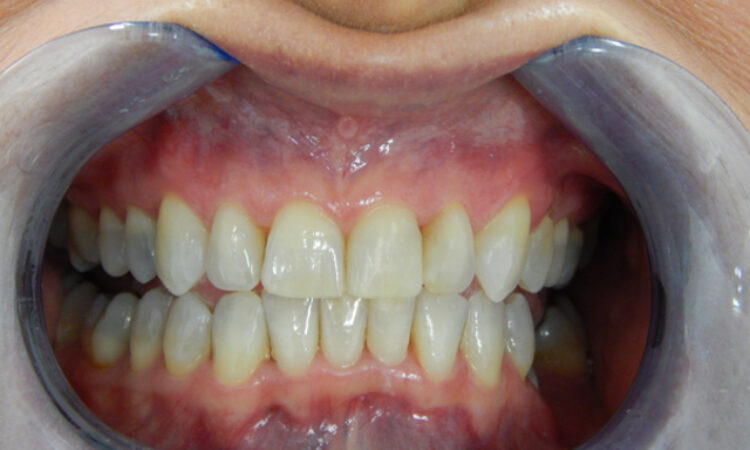

Before - puredental After - puredental

Case 17 - Invisalign®